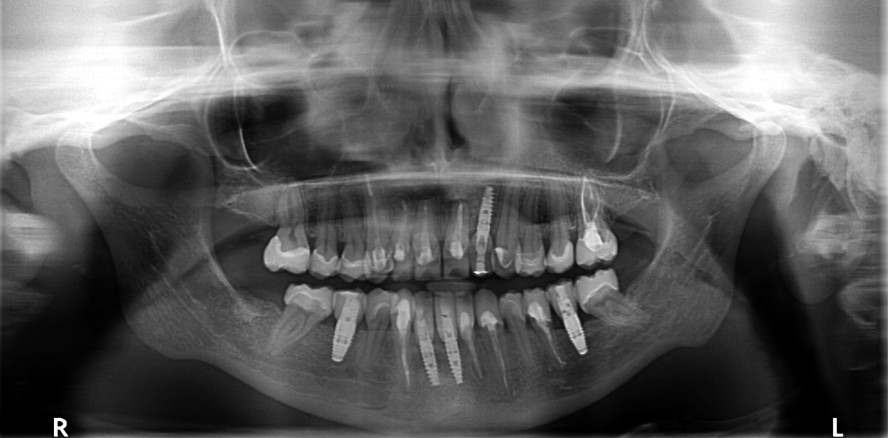

Eine 35-jährige Patientin stellte sich auf Empfehlung eines Kollegen mit einem sanierungsbedürftigen, parodontal (Parodontitis apicalis) geschädigten Gebiss vor. Zudem zeigten sich Verspannungen im Schulter- und Nackenbereich. Sie wies darauf hin, dass sich aufgrund einer angefangenen prothetischen Sanierung in der jüngsten Vergangenheit das Kauvermögen deutlich reduziert und die Gebisssituation besonders in der oberen Front immer weiter verschlechtert hat. Laut eigener Aussage „passen die Zähne nicht mehr richtig aufeinander“, und seit der angefangenen Sanierung im UK „wäre das Kauen nur noch eingeschränkt möglich“. Zudem leidet sie an überempfindlichen Zahnhälsen im Bereich der Prämolaren und Molaren beidseits. Vor ungefähr 15 Jahren wurde laut Patientin die erste „Full-mouth-Rekonstruktion“ in Mazedonien durchgeführt. Die klinische Funktionsanalyse zeigt positive parafunktionelle Befunde (Okklusaler Index 1,4 „kompensiert +“), welche der Patientin klinisch regelmäßig Kopfschmerzen sowie starke Beschwerden beim Kauen und Schlucken verursachen (Abb. 4).

Aus der klinischen und röntgenologischen Befundung leiteten sich die Diagnosen chronische apikale Parodontitiden, Myoarthropathie, Parafunktion – Pressen und Knirschen – mit sichtbarem Zahhartsubstanzabrieb (Attrition) einhergehend mit Verlust der vertikalen Dimension (Kompression der Kiefergelenke), HWS-Syndrom (starke Verspannungen im Schulter- und Nackenbereich, regelmäßig Kopfschmerzen), Störung der statischen und dynamischen Okklusion (Latero- und Protrusionsfacetten FZB und SZB) sowie ein prothetisch und konservierend insuffizient versorgtes Erwachsenengebiss ab. Grundsätzlich stand die Diskussion Extraktion der beherdeten Zähne und Ersatz durch Einzelzahnimplantate oder Brückenrekonstruktionen versus Erhalt (Endo-Revisionen 11, 21, 33, 32, 42 und 43) bei fortgeschrittener apikaler Parodontitis, Alveolarkammdeformation im zahnlosen Kieferabschnitt 22 (Knochendehiszenz), Lockerungsgrad I–II an 12, 11, 21 sowie Rezessionen der Gingiva,14 Verlust der interdentalen Papillen im ästhetischen Bereich, mittelhoher Lachlinie und der ausgedehnte Bedarf an konservierender und prothetischer Behandlung im Raum. Nach Abwägung sowohl ethischer als auch für die Patientin wichtiger psychologischer Aspekte ließ dies den apikal beherdeten und teilweise sekundärkariös geschädigten Zähnen zwar eine fragliche Prognose im Hinblick auf die Langzeitstabilität zuteilwerden, jedoch war durch die umfangreichen Vorsanierungen und das junge Alter der Patientin der Fokus auf Zahnerhalt ausgerichtet. Die Patientin wünschte sich zudem nach Möglichkeit ein anspruchsvolles ästhetisches Erscheinungsbild und war sich des Misserfolgsrisikos der zu revidierenden Zähne bewusst. Dass auch bei parodontal angeschlagenen Zähnen nach entsprechender Vorbehandlung eine vorhersagbare Langzeitprognose formuliert werden kann,15 stand außer Frage, jedoch zu welchem (finanziellen und/oder zeitlichen) Aufwand und auch mit entsprechend (vorhersagbarem) ästhetischem Outcome?